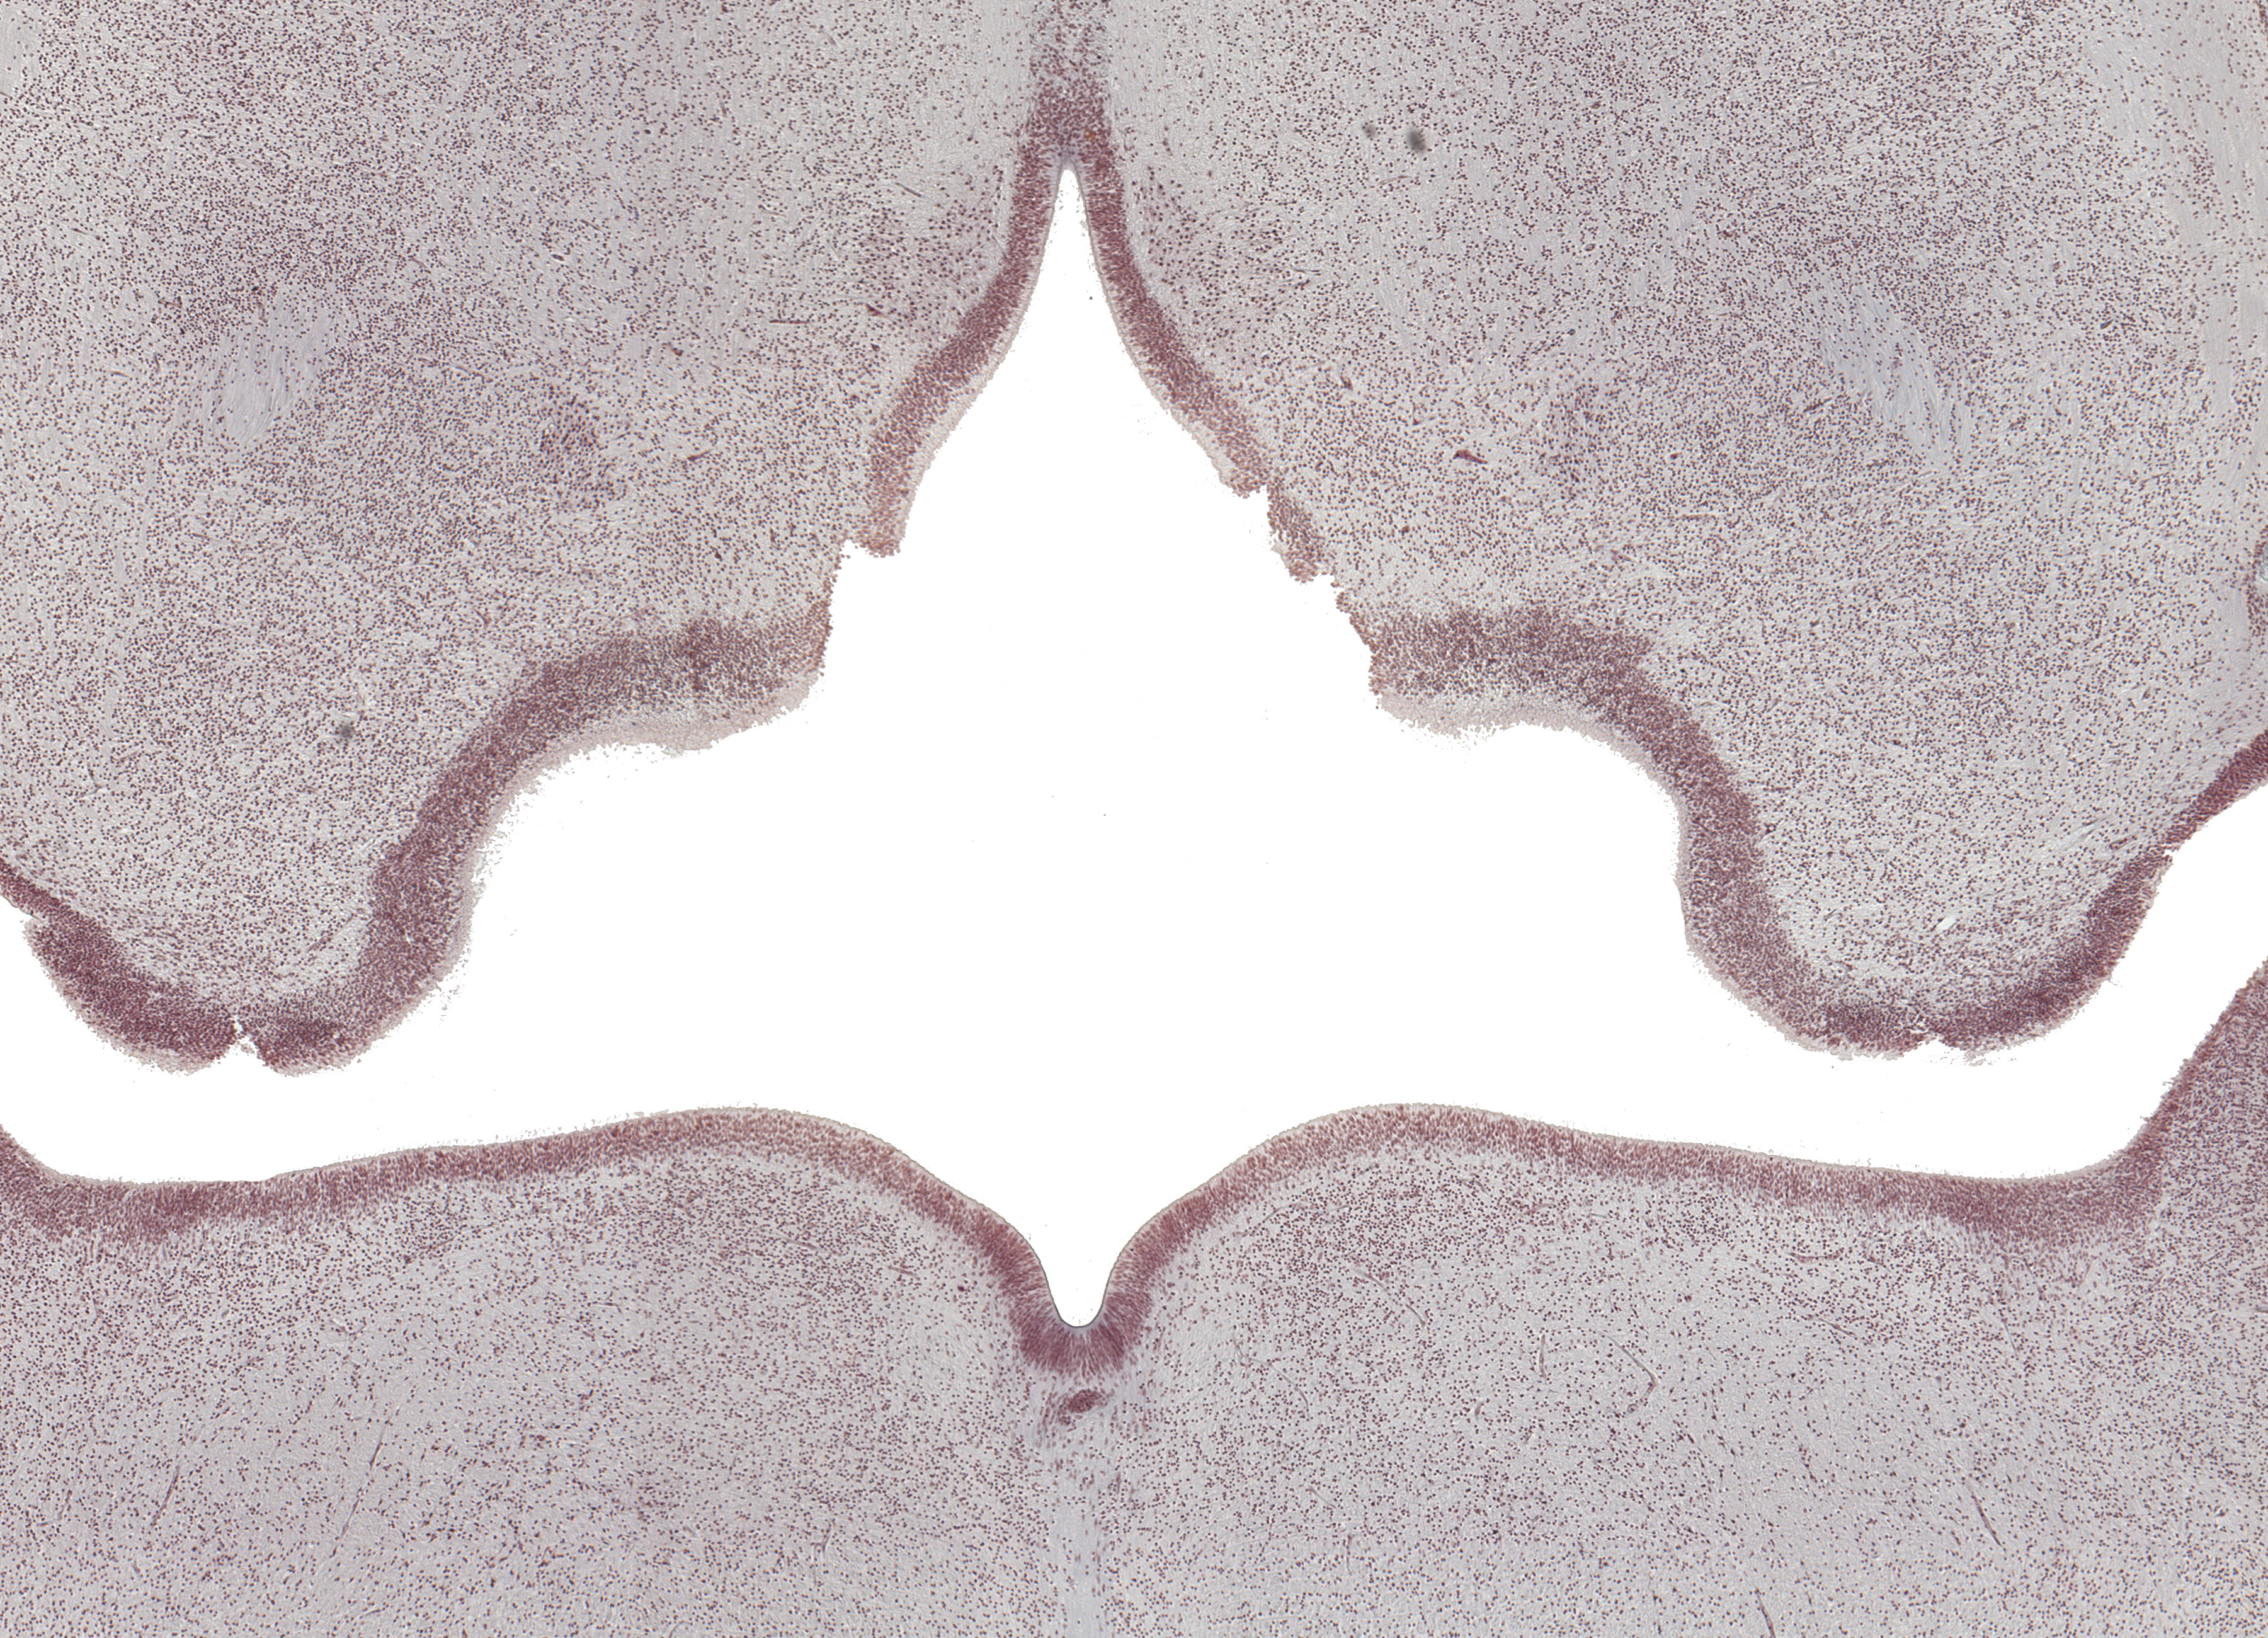

Tissue

–

Floor of Fourth Ventricle

Carnegie Embryo #9226

Location:

43-01-01